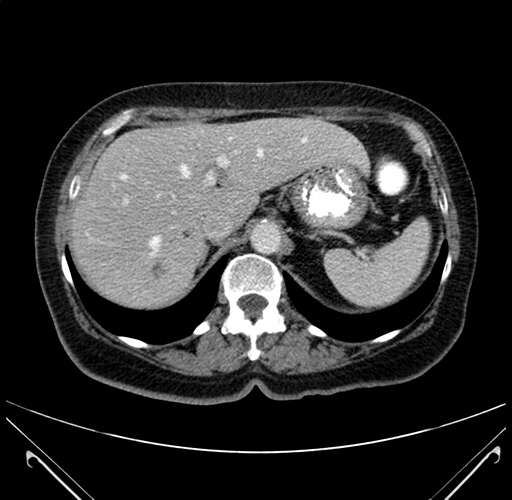

Pre-Chemo: Axial Venous

Axial Venous